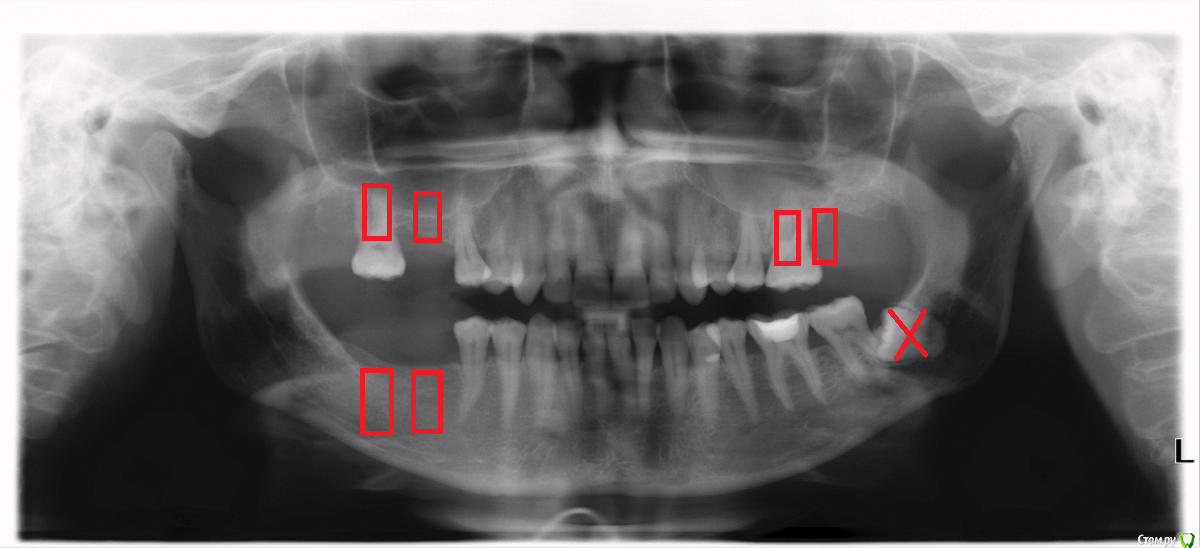

ElenaNorge Опубликовано 16 июня, 2017 Поделиться Опубликовано 16 июня, 2017 (изменено) Здравствуйте уважаемые специалисты!У меня назрел вопрос протезирования. У меня вот такая ситуация с зубами - см. прикрепленный панорамный снимок.Можно ли мне поставить импланты, включая зуб 26 на ВЧ слево, который еще не удален, но очень сильный кандидат на это, так как беспокоит? Какой план имплантирования является наилучшим для моего случая? Заранее благодарю за ответ. С уважением:-) Изменено 16 июня, 2017 пользователем ElenaNorge Ссылка на комментарий

kamranchick Опубликовано 19 июня, 2017 Поделиться Опубликовано 19 июня, 2017 займитесь сначала правой стороной, так сказать, разгрузите левую сторону, как восстановите правую сторону, займетесь левой стороной, чтобы было чем жевать, зуб 2.6 если особо не шатается, можете депульпировать чтобы не болел, и походите с ним какое то время Ссылка на комментарий

Bier Опубликовано 20 июня, 2017 Поделиться Опубликовано 20 июня, 2017 займитесь сначала правой стороной, так сказать, разгрузите левую сторону, как восстановите правую сторону, займетесь левой стороной, чтобы было чем жевать, зуб 2.6 если особо не шатается, можете депульпировать чтобы не болел, и походите с ним какое то времяа за что вы 17й зуб приговорили? Я бы наверху только 1 имплантат, в позицию 16 поставил. С остальным согласен.Что касается перелетов, если операция пройдет без осложнений - летать можно. Если с перфорацией мембраны - летать не рекомендуется. Ссылка на комментарий

ElenaNorge Опубликовано 21 июня, 2017 Автор Поделиться Опубликовано 21 июня, 2017 а за что вы 17й зуб приговорили? Я бы наверху только 1 имплантат, в позицию 16 поставил. С остальным согласен.Что касается перелетов, если операция пройдет без осложнений - летать можно. Если с перфорацией мембраны - летать не рекомендуется.Нет, нет 17 не приговорили, приговорили 26. :-). Насчет операции - все поняла. Спасибо за разъяснение. чем больше у вас будет вопросов, тем больше сомнений у вас будет. доверьтесь своему сердцу и идите к тому врачу которые ближе будет вам по душе. Вот это как раз самое сложное. Живу в Норвегии, здесь один зуб будет стоить где-то 3000 евро. Ищу специалиста в другой стране, скорее всего в Риге . :-) Kamranchickier, Bier - Спасибо большое за ответы на мои вопросы. Ссылка на комментарий